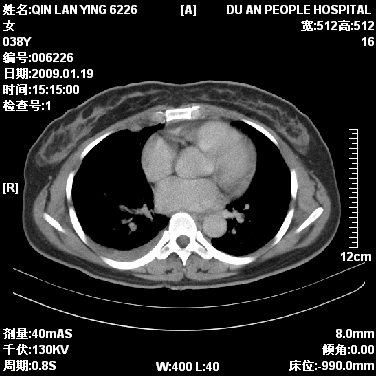

女,38岁,胸疼1个月。wbc:1万4

1)右肺中央型肺癌并右肺上叶阻塞性肺炎、节段性肺不张,纵隔淋巴结转移、右侧胸膜转移、肝脏转移。2)右侧胸腔少量积液。

1、右侧中央型肺癌并阻塞性肺不张,纵隔内、主动脉弓旁、右肺门淋巴结及肝脏转移可能性大,建议纤支镜进一步检查。

本病例有几个容易诊断的地方:1、右肺上叶前段支气管闭塞,肺不张。2、淋巴结明显肿大。3、肝脏多个类圆形低密度影呈“牛眼征”改变,高度提示转移。

从影像学角度分析      右肺上叶中央型肺癌,并阻塞性不张、肺炎,纵隔淋巴结、膈顶淋巴结转移。